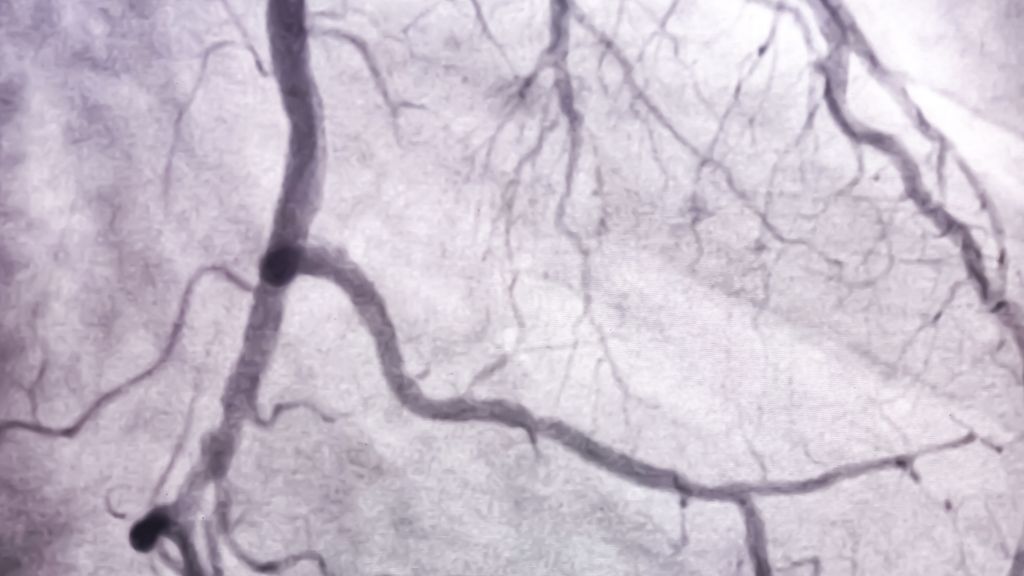

F. Weidinger: Damals war gerade die Anfangszeit der PTCA, der perkutanen transluminalen Koronarangioplastie, die heute als „plain old balloon angioplasty“ – POBA – bezeichnet wird. Alles begann 1977 mit der ersten Ballondilatation durch Andreas Grüntzig in Zürich. Das war sensationell für junge Kardiologen. Es gab plötzlich die Möglichkeit, die koronare Herzkrankheit interventionell zu behandeln. Alle wollten diese Methode erlernen und im Herzkatheter ausgebildet werden. Wenn ich zurückblicke, war das eine sehr spannende Zeit, in der man viele Einblicke in die Mechanismen der koronaren Atherosklerose gewann und die sowohl die Grundlagen- als auch die klinische Forschung enorm vorantrieb. Parallel dazu entwickelte sich die sogenannte Primär-PCI im akuten Herzinfarkt, das ist ca. 25 Jahre her.

F. Weidinger: Zu Beginn mussten die meisten Patienten mit revaskularisationsbedürftiger KHK den Herzchirurgen vorgestellt werden. Das blieb auch lange Zeit so, zumal die Interventionen in der Frühzeit mit einem hohen Restenose- und Komplikationsrisiko behaftet waren. Daher gab es regelmäßige wöchentliche Sitzungen, bei der alle anwesend sein mussten und in der wir unsere Patienten präsentierten. In Wien war in den 1980er-Jahren aber auch die Bypass-Chirurgie noch nicht so etabliert, sodass einige Patienten mit sehr komplexer Erkrankung zum Teil nach Deutschland zur Operation geschickt wurden. Die Weiterentwicklung der Methode zur heutigen „perkutanen Koronarintervention“ (PCI) durch die Einführung von Bare-Metal- und später Drug-eluting Stents und anderen Techniken hat bis in die 2000er-Jahre gedauert. Heute können wir sehr komplexe Fälle interventionell versorgen, wodurch Zuweisungen zur Bypasschirurgie deutlich zurückgegangen sind.

F. Weidinger: Es war genau umgekehrt. Wir haben zunächst die leichten Fälle bekommen und uns mit der Entwicklung der Stents langsam zum Hauptstamm und zur Mehrgefäßerkrankung vorgearbeitet. Wir haben mit proximalen, isolierten, gut angehbaren, kurzstreckigen Stenosen begonnen. Bei der TAVI lief es genau anders herum. Da hat man zuerst die Patienten interventionell behandelt, die für die offene Operation zu krank waren. Inzwischen ist es aber auch mit der PCI so, dass wir Patient:innen mit sehr komplexen Stenosen bekommen, die von der koronaren Situation her eigentlich bessere Kandidaten für die Bypass-Chirurgie wären, die aber zu alt oder zu krank dafür sind.

F. Weidinger: Drug-eluting Stents der ersten Generation hatten dicke „struts“ (Streben), was nicht günstig war. Erst in den 2010er-Jahren kamen die neueren Stents mit dünneren Streben von 60 bis 80µm. Das sind die Stents, die sich schließlich durchsetzten und mit denen wir heute die meisten Patient:innen gut behandeln können. Wesentlich zu bes- seren Ergebnissen beigetragen hat die Entwicklung der heutigen dualen Plättchenhemmung, die die Stentthrombose nahezu eliminierte. Die DAPT(„dual antiplatelet therapy“) mit Clopidogrel und Aspirin bzw. die potenten P2Y12-Hemmer Prasugrel und Ticagrelor haben wesentlich dazu beigetragen, dass die Stentthrombose extrem selten geworden ist und die Stentrestenose heute im einstelligen Bereich liegt. Der Durchbruch der interventionellen Kardiologie schlechthin war jedoch die Behandlung des akuten Herzinfarkts durch Wiedereröffnung des schuldigen Gefäßes und schnellstmögliche Reperfusion. In den 1960er-Jahren lag die Mortalität nach Herzinfarkt im Krankenhaus bei 30%, heute liegt sie bei Patient:innen ohne Schockbei unter 2%. Wir sind seit ca. 15 Jahren auf diesem Niveau und versuchen, noch besser zu werden. Zweifellos ist die „Primär-PCI“ der wesentliche Meilenstein der interventionellen Kardiologie der letzten 30 Jahre gewesen.